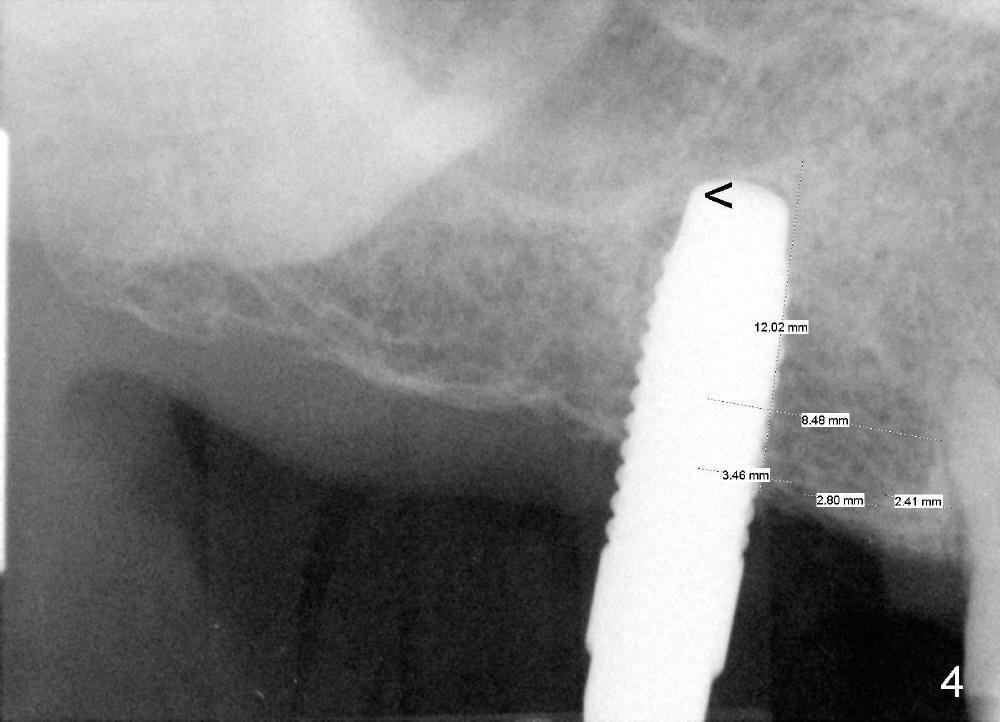

Model surgery indicates that the implant at the site of #3 should be placed 3-4 mm (half the width of a premolar) more distal (Fig.1: CBCT sagittal section). A 7x14 mm tapered soft tissue-level implant appears to be appropriate to the recipient alveolus (Fig.2 coronal section). PA is taken when a 2.0 mm pilot drill makes an initial osteotomy at the depth of 8 mm (Fig.3); the distance between the distal surface of #4 and the center of the osteotomy is equivalent to that of the design (Fig.1). The final depth of the osteotomy is then adjusted at 11 mm.

The pilot drill is easily penetrating the cancellous bone, suggesting low bone density. The remaining osteotomy is finished by bone expanders (Fig.4: 4.3 mm) and taps until 6x14 mm at gingival level. There is no sinus perforation when the 6x14 mm tap is removed from the osteotomy (Fig.5). Sinus lift is observed (Fig.6 arrowheads) when a 6x14 mm implant is placed with insertion toruqe > 60 Ncm. The distance to the adjacent tooth remains consistent to that of design.